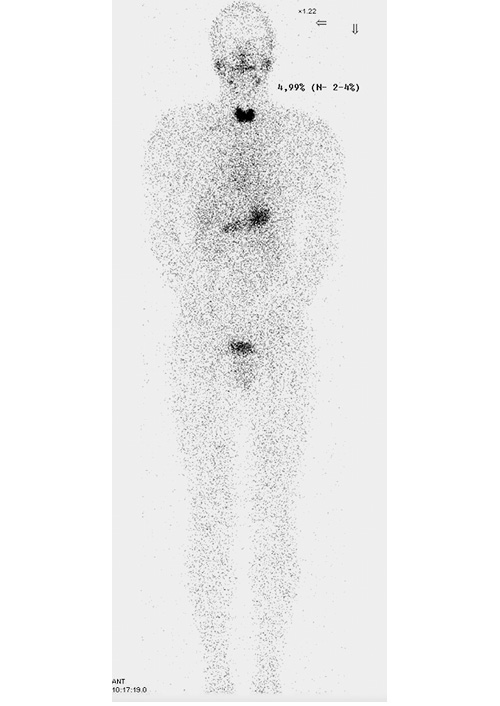

2. Fig. 2. The calculation of the index of the capture of the radiopharmaceutical by the thyroid gland from the account over the whole body. | |